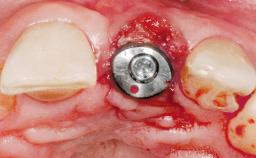

Late Placement of an Implant in a Maxillary Left Central Incisor Site

A 36-year-old female patient was referred for the replacement of the upper left central incisor (tooth 21), which had fractured. Although the tooth had been asymptomatic for many years, the crown began to loosen, at which time she presented to her dentist for an assessment. Teeth 21 and 22 had both been endodontically treated many years previously. She was a healthy individual and a non-smoker.

| Bone Augmentation | Horizontal|Staged |

| Augmentation Materials | Xenogenous|Membrane |

| Soft Tissue Grafting | Simultaneous |